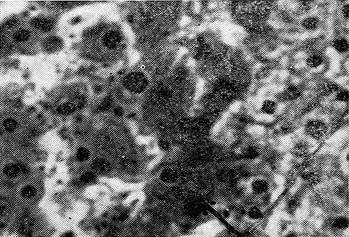

Гистоструктура печени больной А., 50 лет. Стрелкой указаны гиперплазированные М-клетки печени. Окраска гематоксилин-эзоином. X500.

Патологоанатомический диагноз: гиперплазия М-клеток печени (апудопатия). Гипертоническая болезнь, гипертрофия левого желудочка сердца. Небольшой очаг серого размягчения в затылочной области левого полушария мозга в стадии рубцевания. Отек вещества головного мозга. Общий атеросклероз с преимущественным поражением церебральных сосудов. Атеросклеротический кардиосклероз. Мускатная печень. Хронический бронхит, краевые ателектазы нижней доли правого легкого. Ожирение III стадии. При гистологическом изучении препаратов печени были обнаружены островки гиперплазии светлых полигональных клеток, по-видимому, относящихся к М-клеткам (см. рис.), которые продуцируют серотонин, мелатонин и, возможно, катехоламины. Стрессовая ситуация, вероятно, спровоцировала массивный выброс биогенных аминов гиперплазированными апудоцитами у больной, страдавшей гипертонической болезнью, системным атеросклерозом, ожирением, сахарным диабетом, хроническим бронхитом. Гиперсеротонинемия, гипермелатонинемия, гипер-катехоламинемия объясняют появление тахикардии, стойкой гипертонии, гипертермии, бронхоспазма и ателектазов в легких, коллапса, астении. Тяжелые обменные нарушения и гипертермия привели к отеку мозга и летальному исходу. Весьма вероятно, что причиной всех клинических проявлений у больной являлась первичная апудопатия М-клеток печени, но, возможно, обменные нарушения, сердечно-сосудистая патология, напротив, вызвали развитие вторичной апудопатии. Провести дифференциальный диагноз между вторичной и первичной апудопатией в данном случае не представлялось возможным.